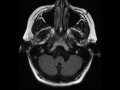

Cerebellopontine Angle Epidermoid

Centered within the left cerebellopontine angle and with extension into the premedullary space, there is a T1-hypointense, FLAIR-hypointense, T2-hyperintense, nonenhancing mass with diffusion restriction. There is deformity and posterior displacement of the inferior aspects of the left greater than right cerebellar hemispheres. The findings are compatible with an epidermoid. Epidermoids are secondary to inclusions of ectodermal tissue within the CNS. Epidermoids contain only squamous epithelium. Epidermoids can appear like a complex arachnoid cyst, but will markedly restrict diffusion. Differential diagnosis includes craniopharyngioma, arachnoid cyst, and lipoma.